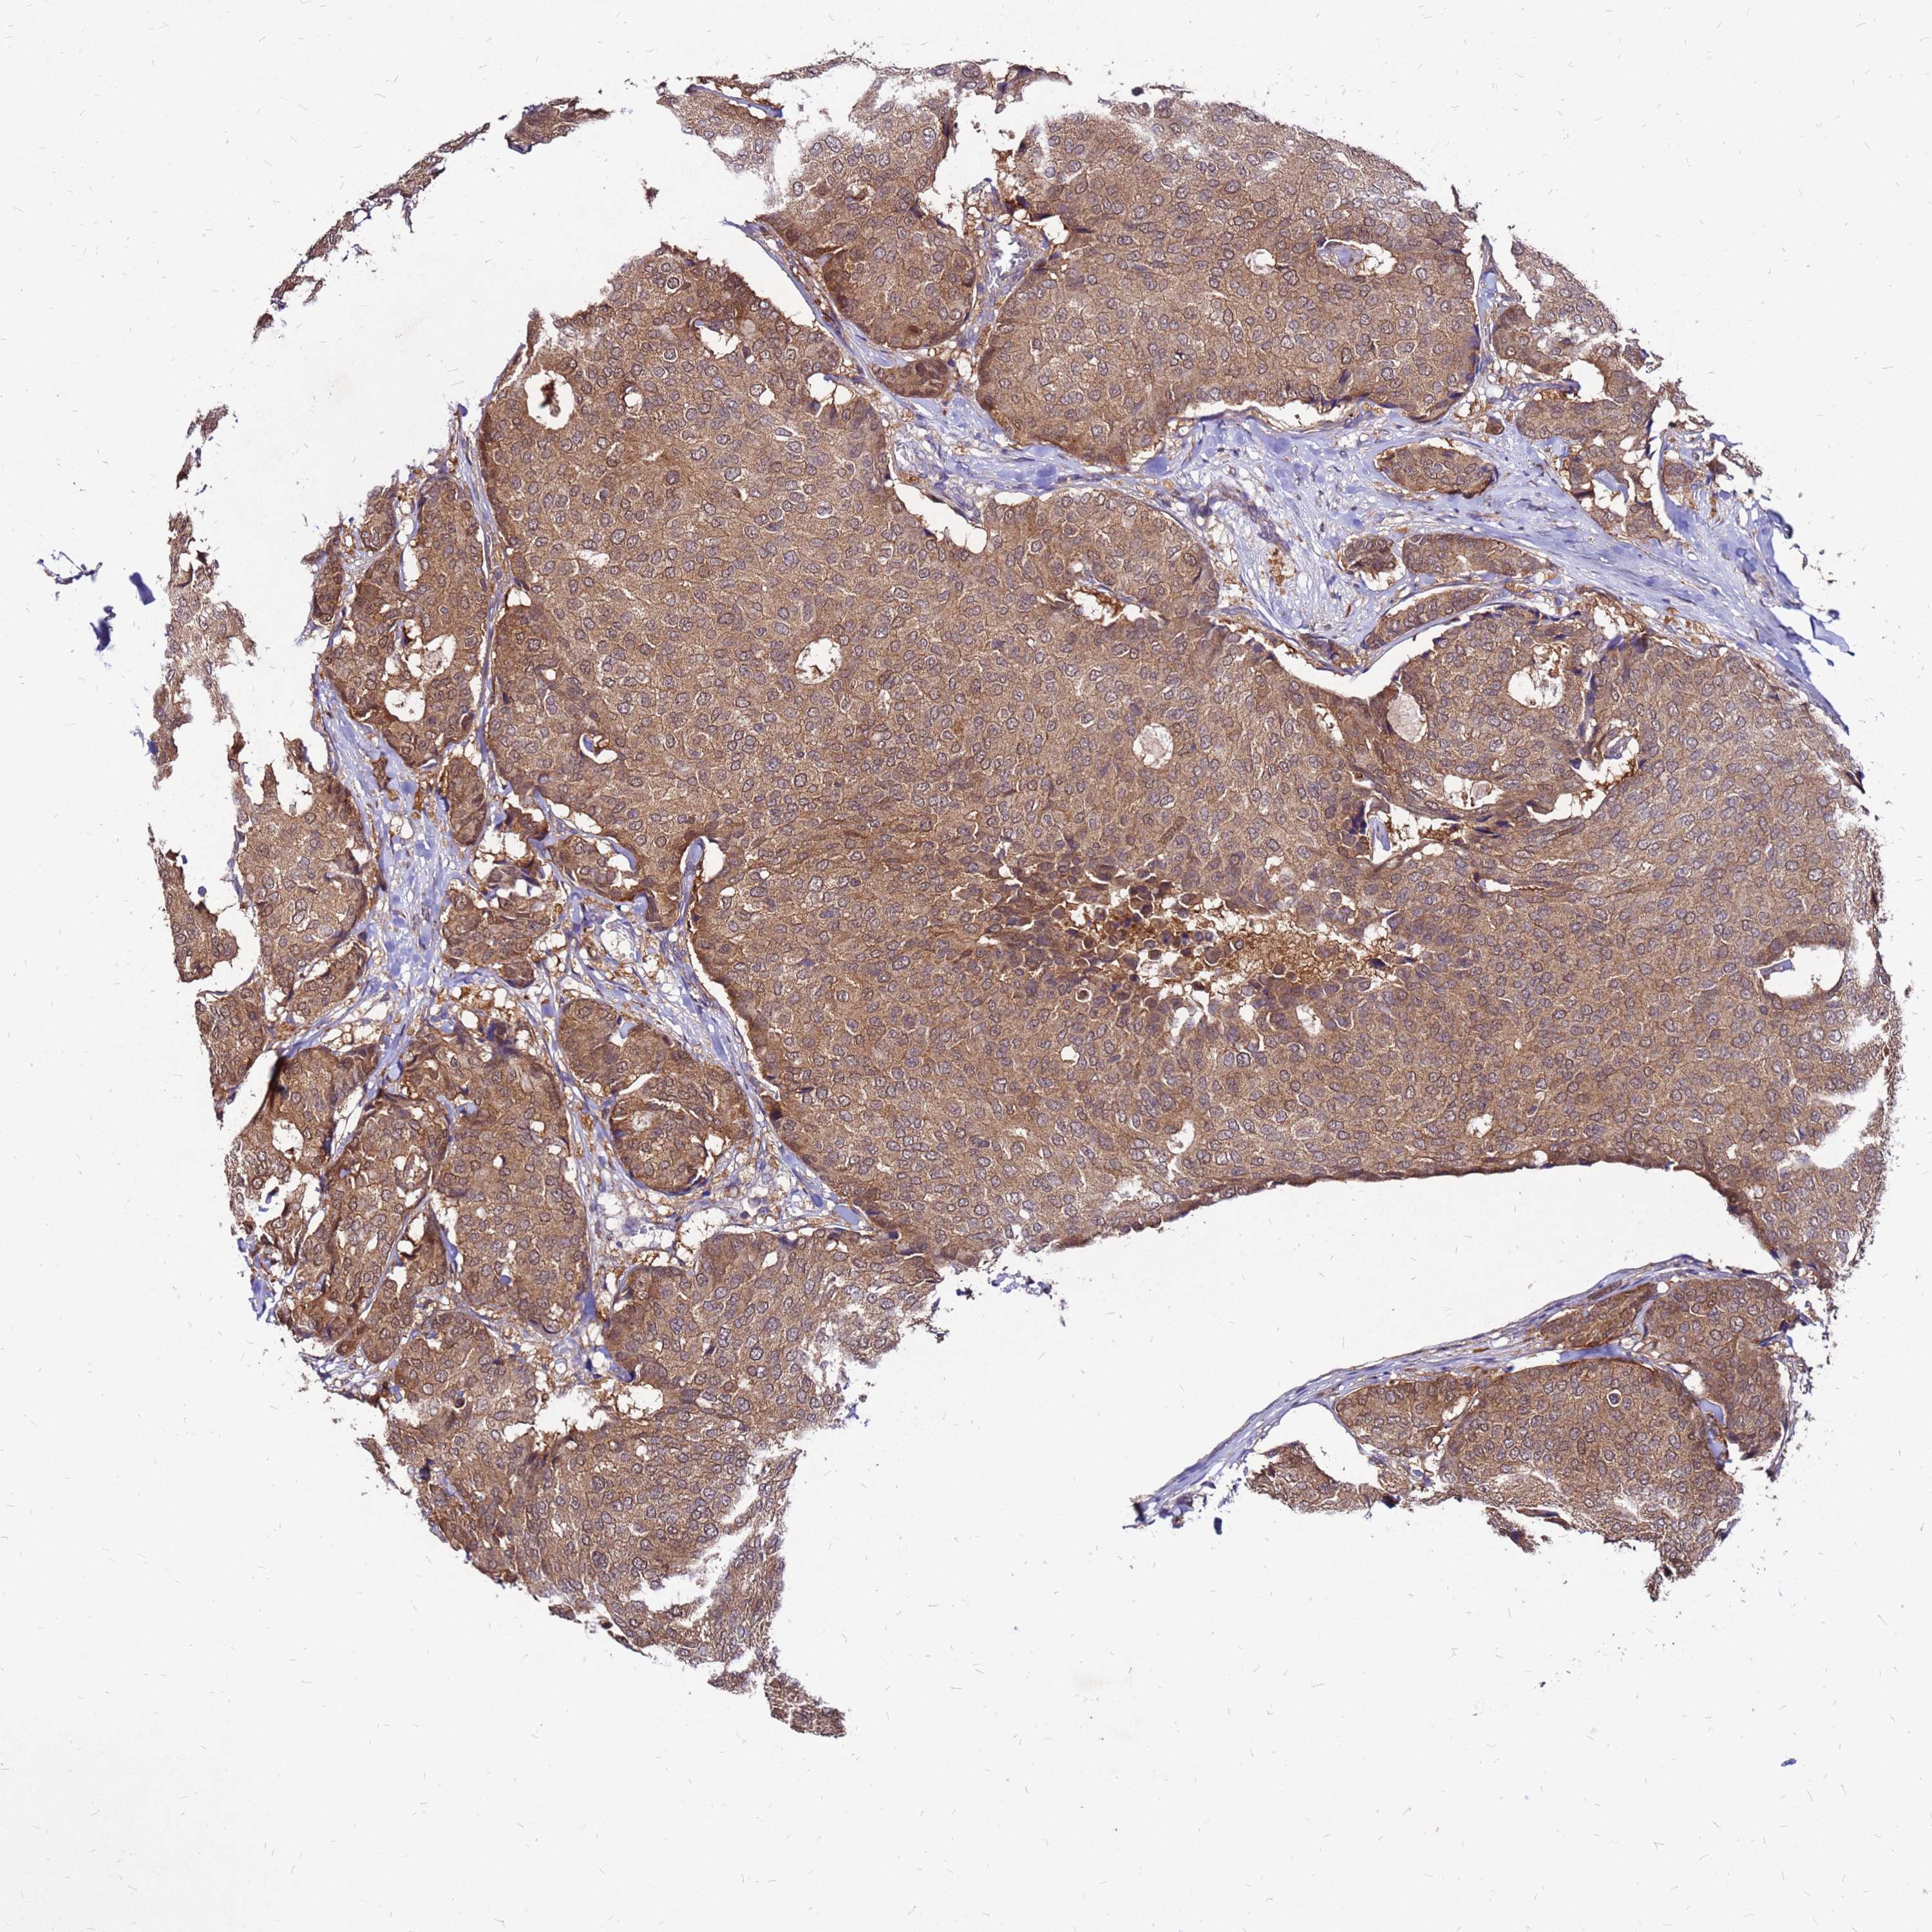

CANCER BREAST CANCER Show tissue menu

BRCA TCGA BRCA VALIDATION PROTEIN EXPRESSION

ANTIBODIES

AND

VALIDATION